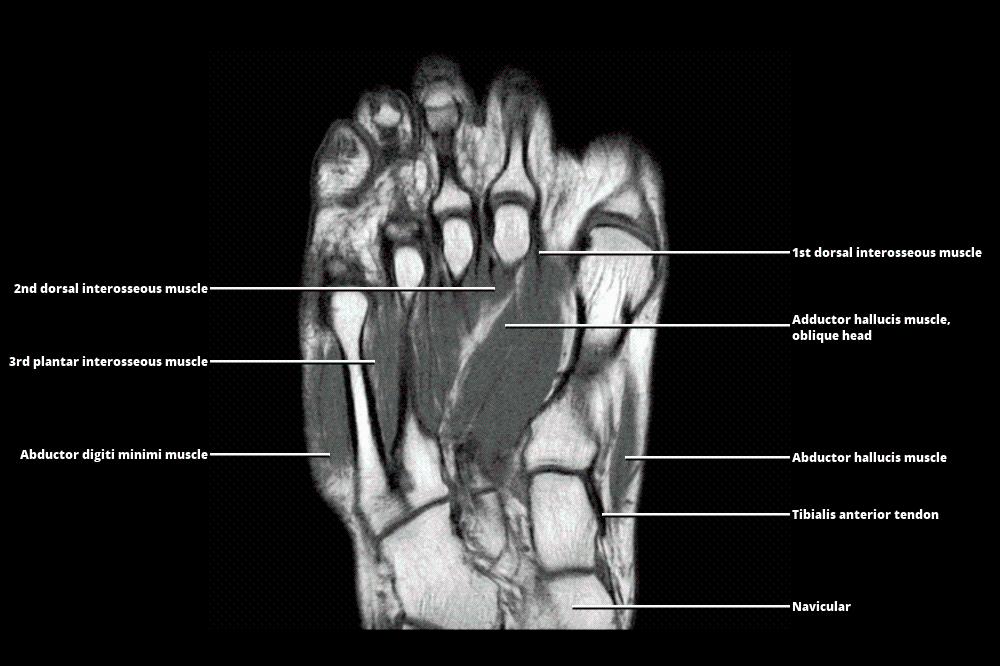

MRI - FOOT

www.wangmd.com

www.wangmd.com

mri atlas

MRI - FOOT

www.wangmd.com

www.wangmd.com

mri

MRI - FOOT

www.wangmd.com

www.wangmd.com

mri